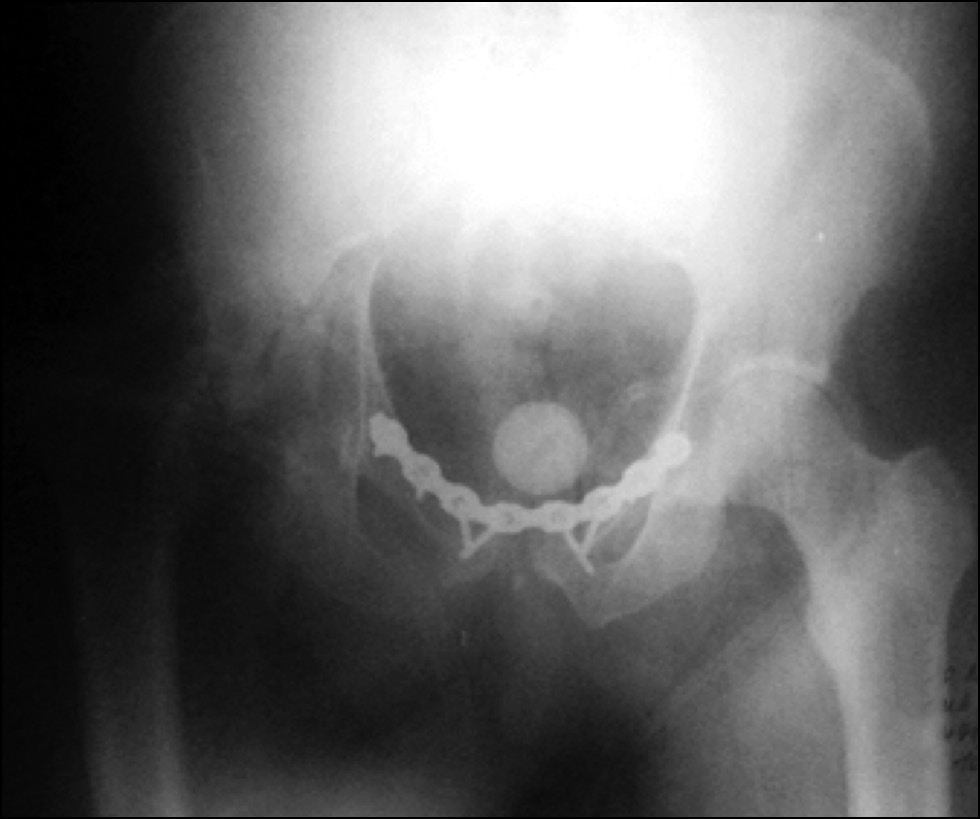

Клинический пример № 1. Пациент, 52 года, травма в результате дорожно-транспортного происшествия 1 год 1 мес назад. По месту травмы проводилось консервативное лечение со скелетным вытяжением за бугристость правой большеберцовой кости в течение 1 мес. Пациент поступил в первое отделение ФГБУ НМИЦ ТО им. Н.Н Приорова спустя год после травмы с диагнозом: «Застарелый разрыв лонного сочленения. Неправильно срастающийся перелом правой вертлужной впадины. Асептический некроз головки правой бедренной кости. Застарелый вывих головки правой бедренной кости. Разрыв правого и левого крестцово-подвздошного со-членения» (рис. 1).

Рис. 1. Пациент, 52 года. Рентген через 1 год после травмы: а — прямая проекция, b — краниальная проекция

Fig. 1. Patient, 58 years old. X-rays 1 year after injury: a — frontal, b — out-let